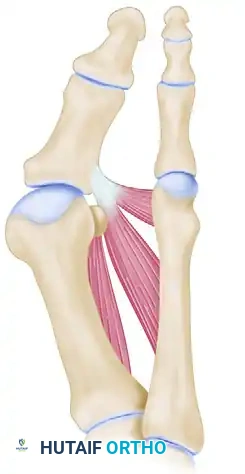

3. The Proximal Phalangeal Osteotomy

This is the most critical phase of the procedure. Precision in the osteotomy cuts dictates the final alignment and stability of the hallux.

- Exposure: Return to the initial medial incision. Use small, right-angle retractors (such as Senn or Ragnell retractors) to protect the dorsal and plantar soft tissues.

- First Osteotomy Cut (Distal): Begin the proximal phalangeal transverse osteotomy 6 to 8 mm distal to the MTP joint articular surface. The cut must be parallel to the apex of the concavity of the proximal articular surface of the phalanx. Utilize a power oscillating saw with a 4-mm-wide blade.

- Lateral Cortex Preservation: It is imperative to cut through the medial, dorsal, and plantar cortices while leaving the lateral cortex intact to act as a mechanical hinge.

- Second Osteotomy Cut (Proximal): Begin the second osteotomy 3 to 4 mm distal to the first cut. Direct the saw blade obliquely and proximally so that it intersects the first osteotomy precisely at the lateral cortex.

💡 Clinical Pearl: Preventing Dorsiflexion Malunion

When making the osteotomy cuts, ensure the saw blade is perfectly perpendicular to the longitudinal axis of the phalanx in the sagittal plane. A plantar-convergent wedge will inadvertently cause a dorsiflexion malunion of the hallux, leading to loss of toe purchase and transfer metatarsalgia.

4. Deformity Correction and Osteoclasis

- Wedge Removal: Carefully remove the excised wedge of cancellous bone by gently rocking it back and forth with a small Kocher clamp or a towel clip.

- Osteoclasis: Close the osteotomy by applying a gentle, steady valgus force to the distal phalanx, creating a greenstick fracture (osteoclasis) of the intact lateral cortex.

- Rotational Correction: During the closure of the osteotomy, a few degrees of pronation of the hallux (often present in hallux valgus) can be simultaneously corrected by gently supinating the toe as the bony surfaces are compressed.

- Medial Flare Resection: If the medial flare of the base of the proximal phalanx produces an annoying bony prominence after closure, it can be carefully resected with a rongeur to ensure a smooth medial contour.